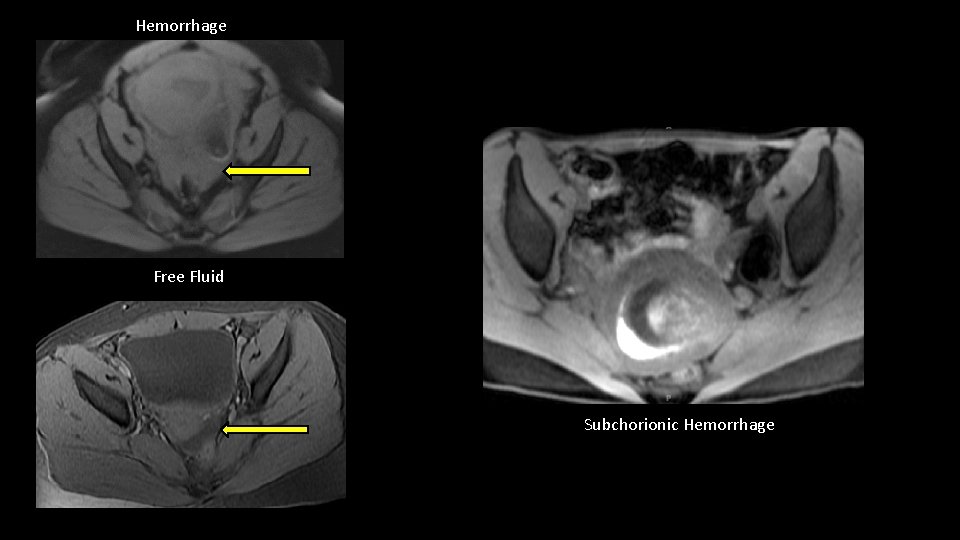

Fat Suppressed T 1 weighted gradient echo sequences can make identifying blood products easier.

Hemorrhage Free Fluid Subchorionic Hemorrhage